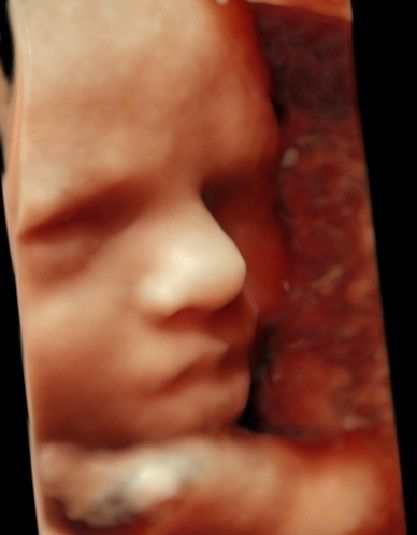

Stale rozwijam swoją wiedzę teoretyczną, jak i praktyczną uczestnicząc w licznych szkoleniach i konferencjach. Posiadam wszystkie cenione certyfikaty pozwalające mi na prowadzenie diagnostyki prenatalnej w pełnym zakresie z corocznym audytem (poprzedni rok oparty na badaniach ponad 400 pacjentek w I trymestrze)

-certyfikat The Fetal Medicine Foundation (FMF) w zakresie badań prenatalnych w 11–13+6 tygodniu ciąży – przezierność karku u płodu (NT); kość nosowa u płodu (NB); przepływ w przewodzie żylnym u płodu (DV); przepływ na zastawce trójdzielnej (TR) oraz oceny ryzyka wystąpienia preeklampsji (stanu przedrzucawkowego) w ciąży.

W swojej pracy specjalizuję się przede wszystkim w DIAGNOSTYCE PRENATALNEJ, MEDYCYNIE MATCZYNO-PŁODOWEJ, oraz ENDOKRYNOLOGII GINEKOLOGICZNEJ.